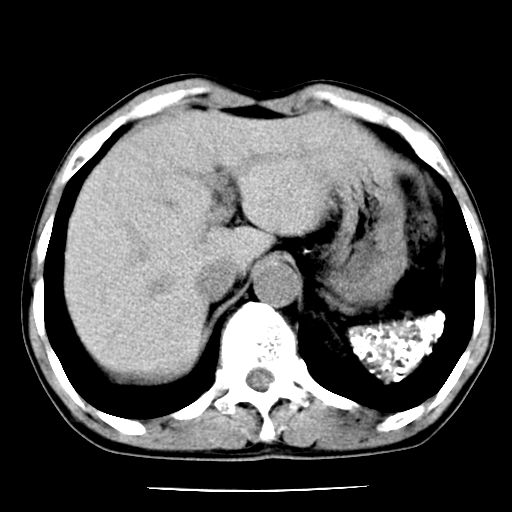

男,59岁,“结核性胸膜炎”30余年,胸部经常疼痛,多次x检查提示“肺部”炎症。腹部疼痛5日,b超提示:“肝内短管结石,余显示不清,建议进一步检查。”

两肺结核并右侧胸腔积液;脾脏、腹腔及腹膜后淋巴结结核[陈旧性];肝内胆管结石

胸部腹部都是结核(双肺。纵隔淋巴结,肝脏,脾脏,肠系膜)

两肺结核并右侧胸腔积液;脾脏、腹腔及腹膜后淋巴结结核[陈旧性];肝内胆管结石。直肠息肉?